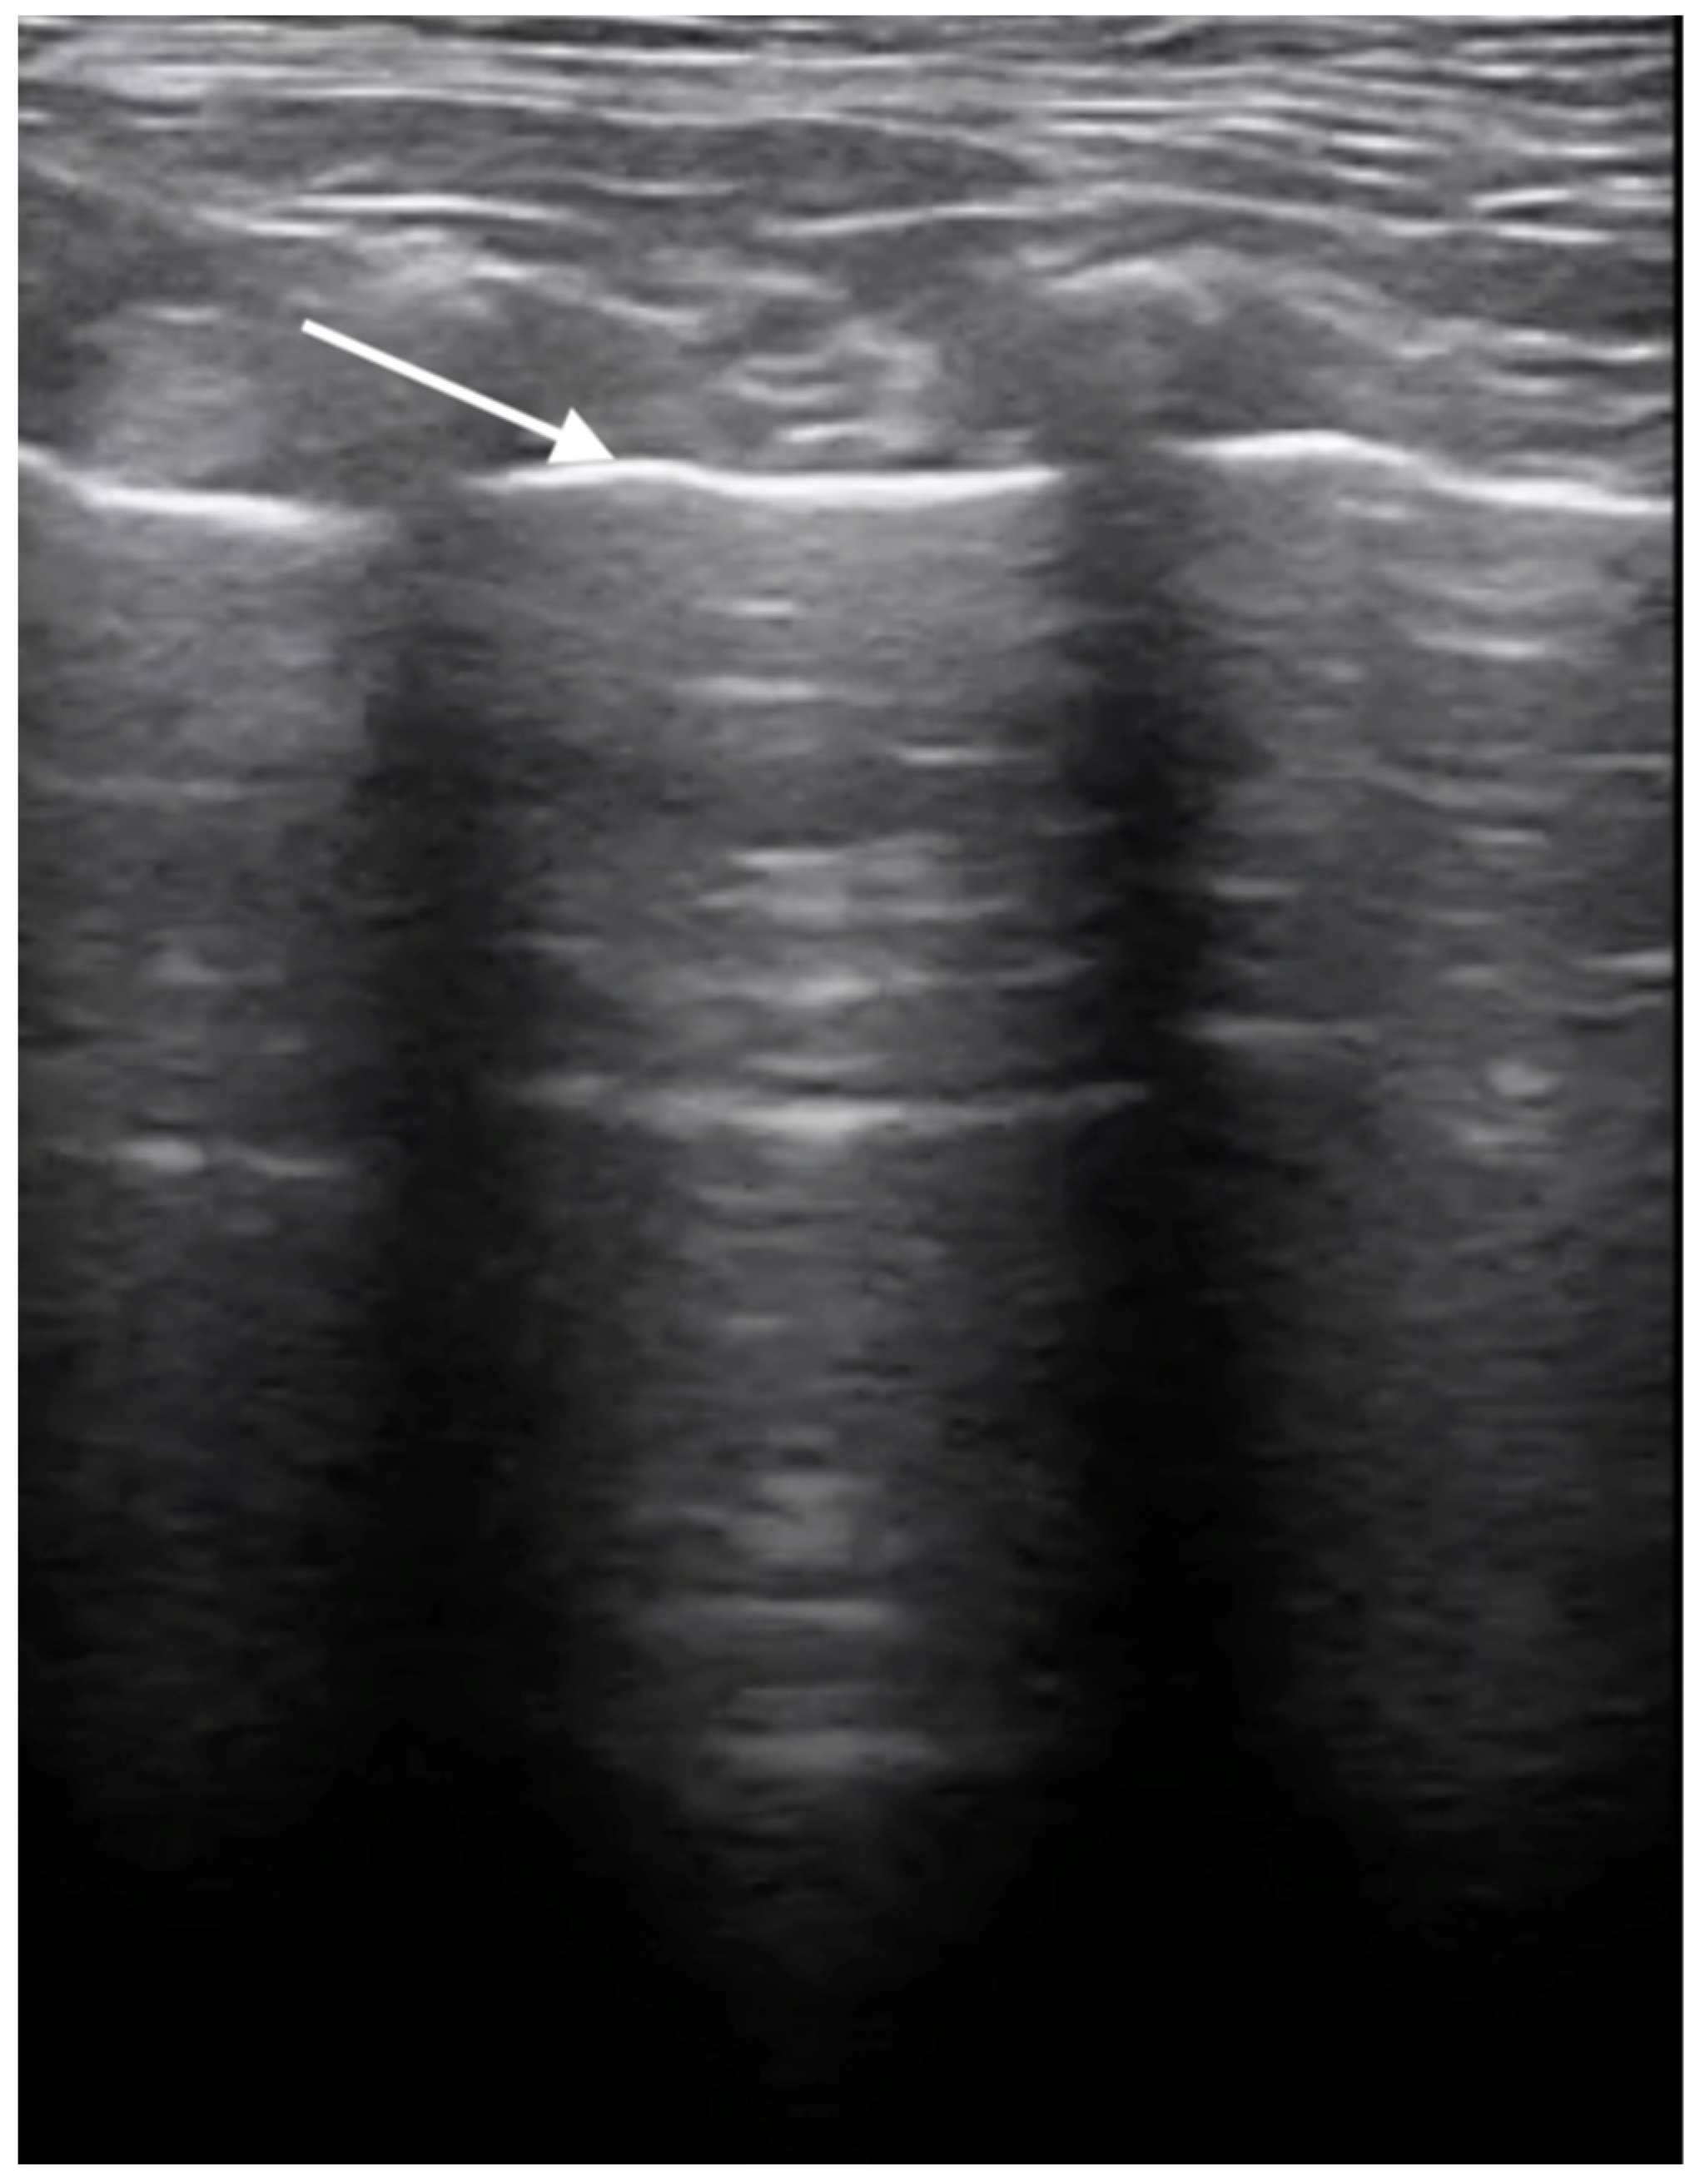

No pathological changes were detected in the lung parenchyma image in the X-ray (Figure 1 and Figure 2). The ultrasound examination revealed in all views a normal, aerated lung pattern. The pleural line was intact, and A-line artifacts were present (Figure 3). The sliding sign was also observed. Echocardiography revealed a mild thickening of the mitral valve leaflets and a slight regurgitation (Figure 4) of this valve. The size of the heart chambers was within the normal range, and myocardial contractility was normal.

Figure 3.

Ultrasonographic examination of the lungs. Image of a healthy lung filled with air; the white arrow indicates the normal, smooth pleural line.